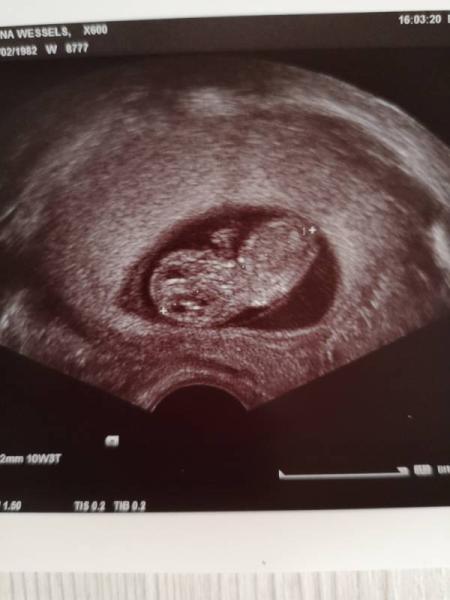

....und alles ist so wie es sein soll. Das Krümelchen hat geschlafen und ließ sich auch durch leichtes stupsen nicht stören Aber Herzchen schlug und das Gehirn könnte ich sehen, 10 Finger, einen geschlossen Rücken....alles fein Morgen geht's in die 12. SSW...so langsam wird es entspannter. Nächster Termin ist in vier Wochen. Liebe Grüße und einen schönen Abend!

Bild zu Heute FA Termin gehabt.... - Forum für April - Mamis